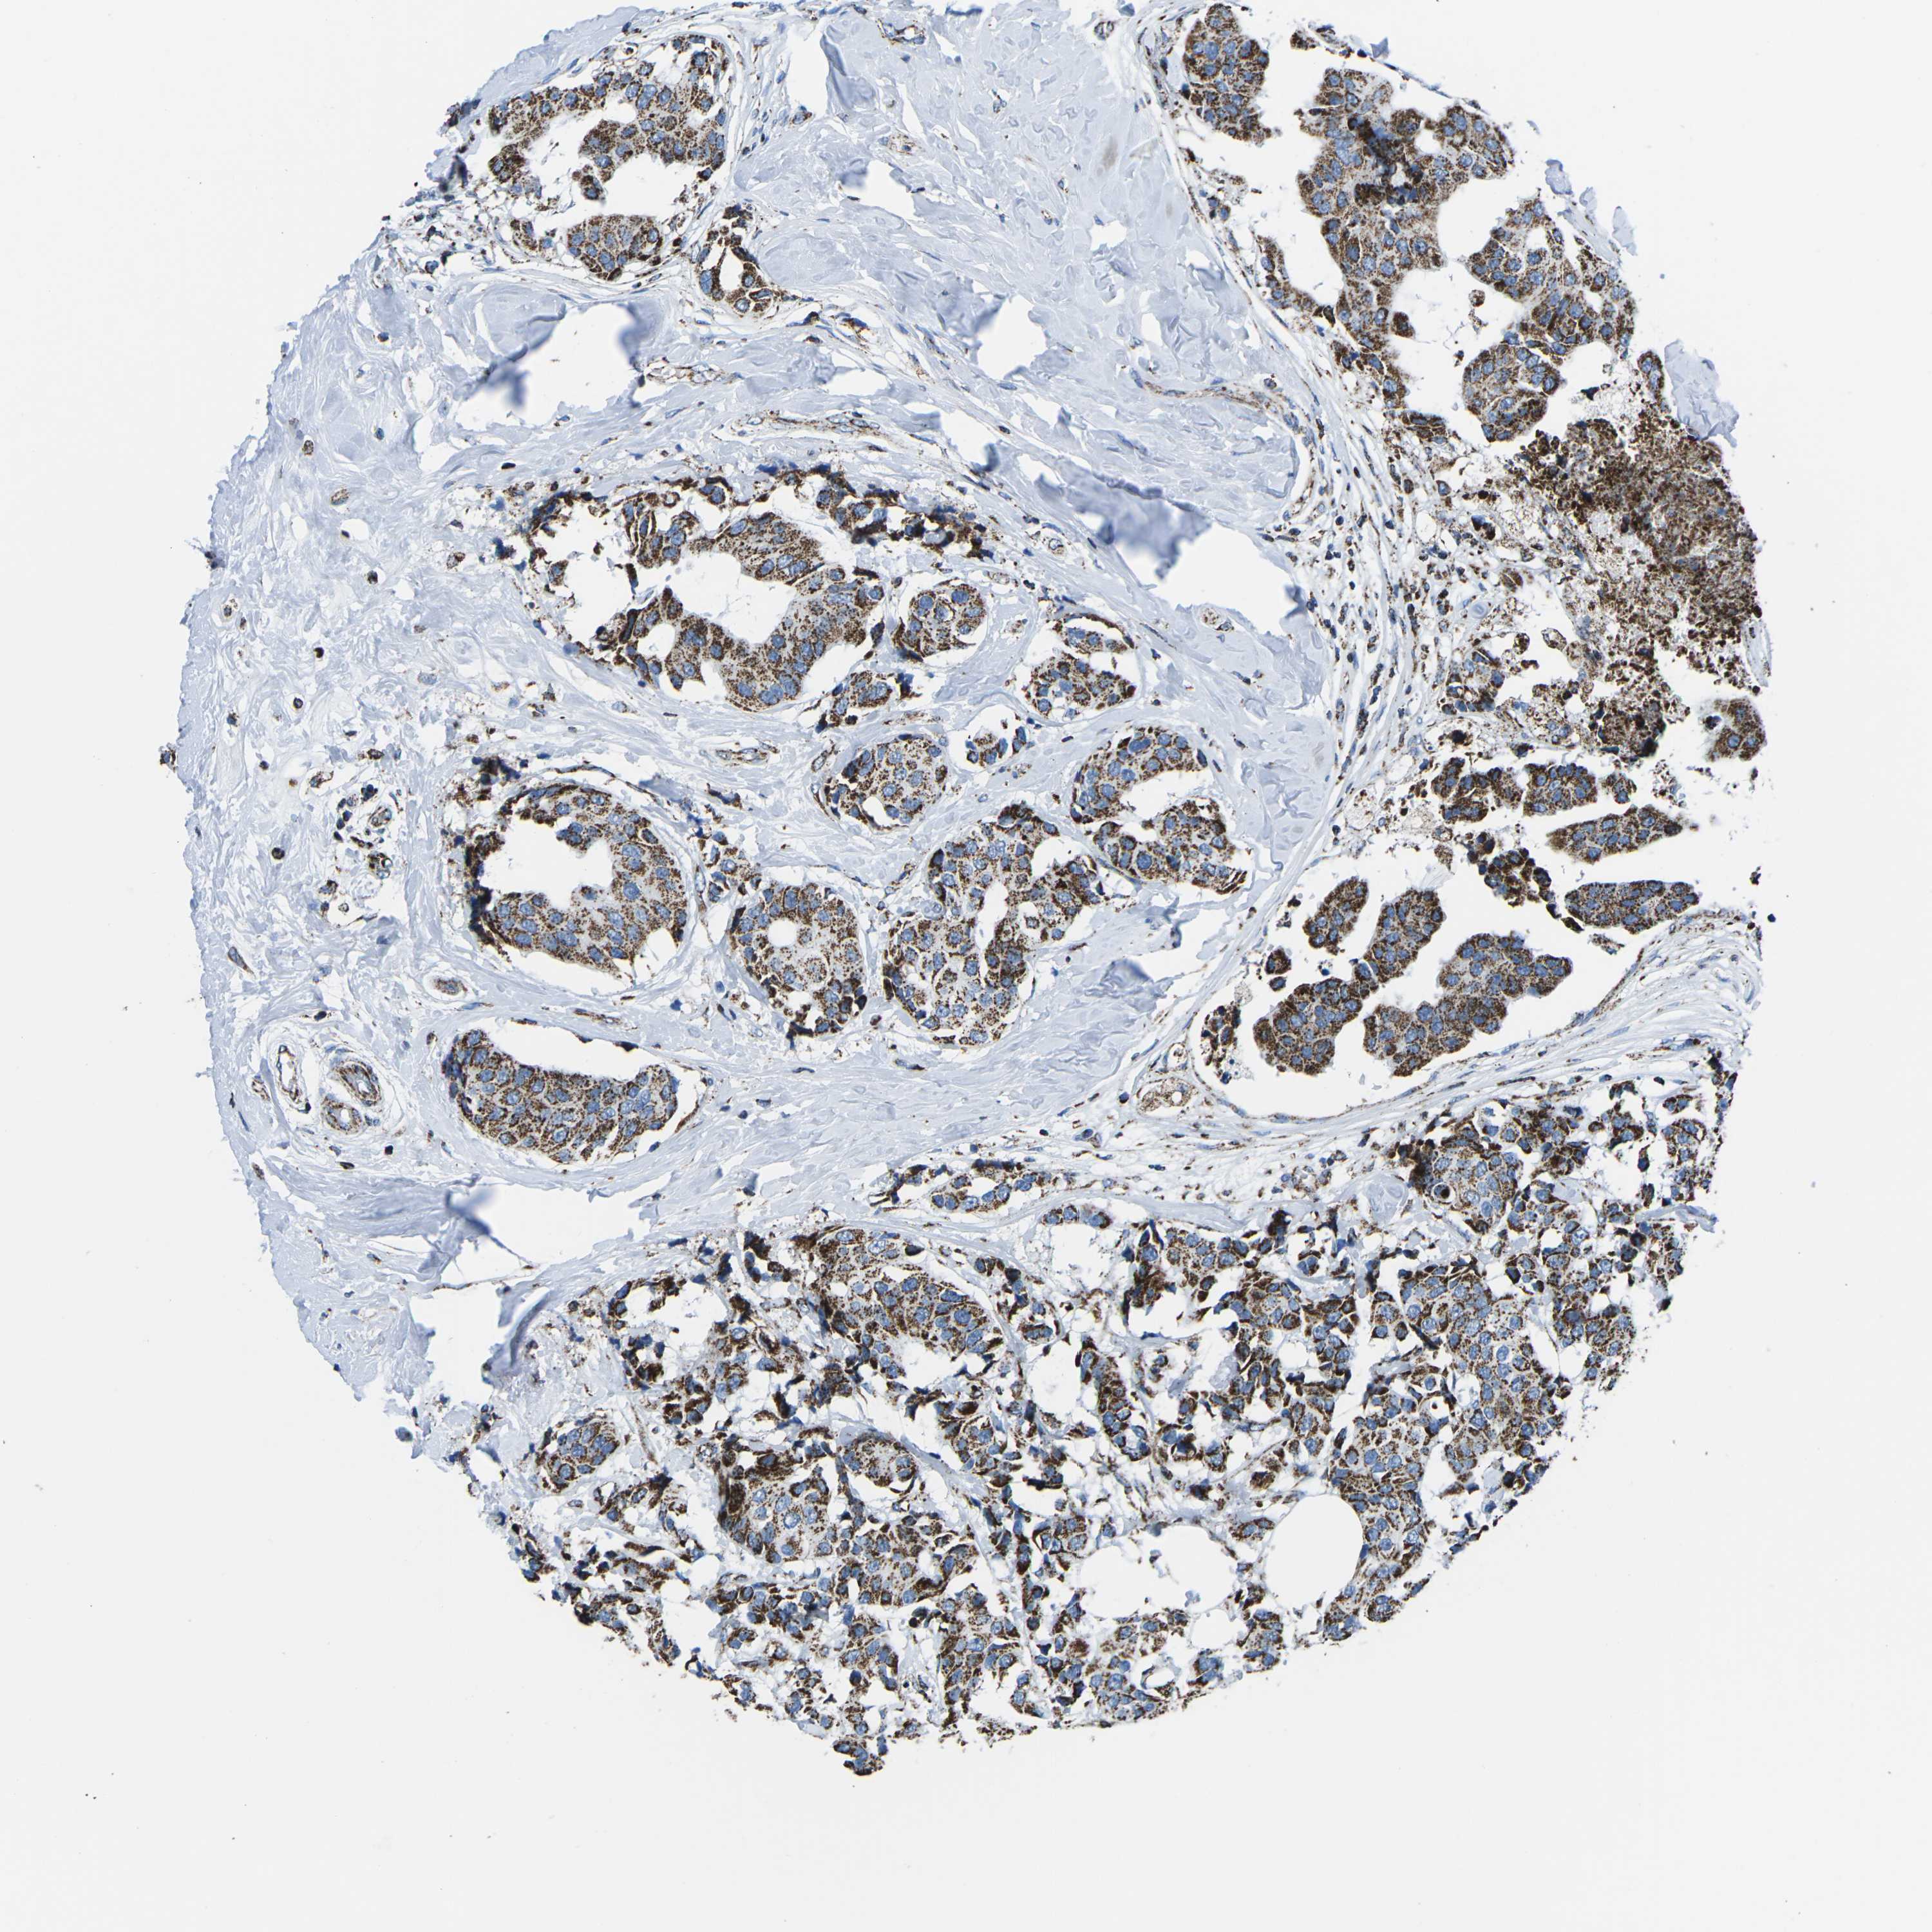

CANCER BREAST CANCER Show tissue menu

BRCA TCGA BRCA VALIDATION PROTEIN EXPRESSION

Breast cancer

Human cancer